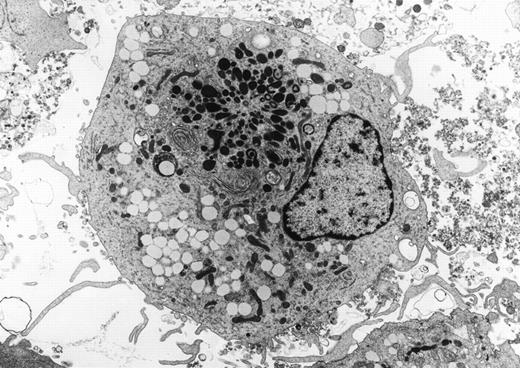

Human dendritic cell derived from peripheral blood progenitors with recombinant interleukin-4 and granulocyte-macrophage colony-stimulating factor (GM-CSF). The cells have long microvillous surface processes and numerous cytoplasmic lysosomes in addition to a well-formed golgi apparatus (uranyl acetate, lead citrate, original magnification ×2,500). (Courtesy of Jonathan W. Said, Kai Chien, Walter Verbeek, Jeffrey Weber, H. Phillip Koeffler, UCLA Center for the Health Sciences, University of Southern California, and Cedars Sinai Medical Center, Los Angeles, CA.) {/ANNT;80256n;;center;0n}